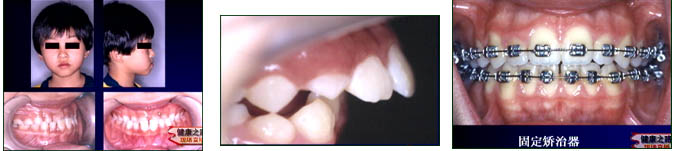

主持人:不整齐的牙齿排列又是怎样的呢? 贾绮林:如图:不整齐的牙齿医学上称之为错合畸形,这是一个下颌前突反颌的病人,俗称地包天。另外一张图中,左上图上牙盖住下牙的范围大大超过了3毫米,称之为上颌前突,俗称龅牙。下图中的错合畸形称为开颌,由于上下颌完全吻合不上,这会严重影响到对食物的切割。第三张图中牙齿的咬合不是正常的牙尖与尖窝的咬合关系,是一种尖对尖的咬合关系。第四张图中,牙齿的排列虽然还比较整齐,但是闭不上嘴,这也是一种错合畸形。 张丁:造成错合畸形的原因很多,主要有两大类:一种是由遗传造成的,另一种是由于后天的环境因素造成的。

主持人:如果孩子牙齿出现不整齐的情况,什么时候进行矫治比较好呢? 张丁:一般来讲对于大多数病人都需要等到牙齿替换完以后(12岁左右)开始正畸治疗比较合适,但是有一些情况需要早期治疗。如图:这是一个地包天的患者,脸形已经是一个月牙形的脸了,应该早期治疗,甚至于在乳牙阶段就应该开始治疗,我们最早治疗的病人大概在4岁左右。来看另一张图,孩子的牙齿突在外面很多,上颌骨也比较向前突,这种情况应该在生长发育还没有结束时及时治疗,限制上颌骨的发育,促进下颌骨的发育。 贾绮林:矫正牙齿通常是用矫正器进行矫正。如图:这是一个固定矫正器,每一颗牙齿上都有一个金属的托槽,托槽是粘在牙齿上的,自己是无法取下来的,必须一直戴着,固定矫正器适合于绝大多数的错合畸形。来看另一张图,这是一个活动矫正器,病人自己可以进行摘戴,这种矫正器需要病人进行配合,戴上后伸舌头就不是很方便了,迫使患者改正不良习惯。 张丁:牙齿是生长在骨骼里的,人体的骨骼是非常活跃的,特别是牙槽骨,一生都在进行不断的改建。矫正器是把力量加在牙齿上,通过牙齿把力量传到牙槽骨,牙槽骨有一个特点,受到压力后会发生吸收,受到牵拉的力量就会有新生,这样在压力的作用下一侧吸收、一侧新生,牙齿就会逐渐在骨骼里改变位置,按照需要处于正确的位置。这就是矫正牙齿的原理。